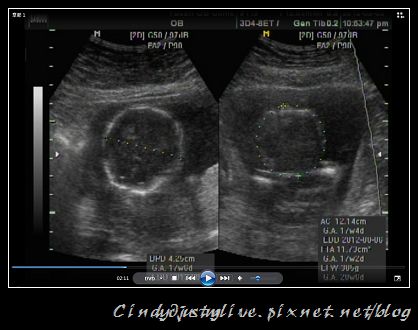

照超音波要量頭圍、肚圍,看來是個頭好壯壯的寶寶,體重預估是385G!